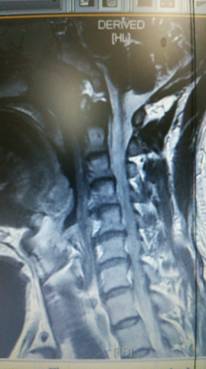

頚椎ヘルニアを専門に治療する整骨院です。交通事故むち打ち治療

手術を考慮された患者さんです。

そもそも医者と患者では、手術に対する意識に大きなギャップがある。その「埋められない溝」について

「患者さんは手術成功と聞くと、『今ある苦しみから解放される』と期待します。一方で、医者としては『このまま放っておくと、亡くなってしまうが、手術することによって寿命が延びる可能性が高まる』という視点。患者側は劇的な改善を求めるのに対し、医者側は命を助けることを最優先にしている。

医学論文の一般的な定義でいうと、『オペ後30日以内』に死亡したかどうかが指標になる。つまり30日生きていれば、患者の回復レベルがどうであれ、手術は『成功』としてカウントされるのです」